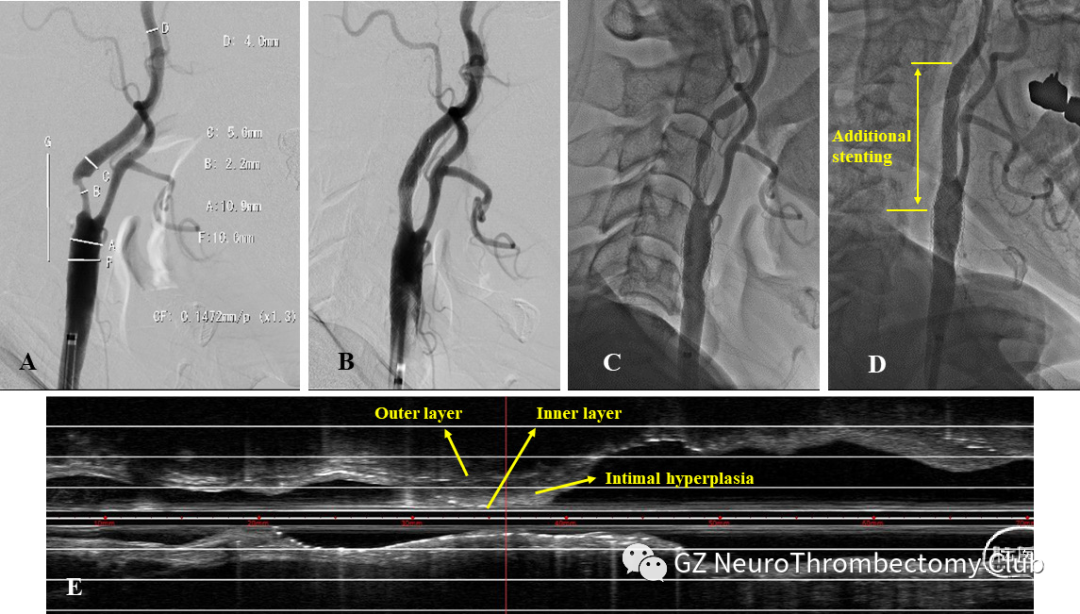

前图再狭窄病例3,一名轻型卒中的成年患者使用CASPER支架(10-30mm)对75%的软斑块狭窄进行了颈动脉支架术(CAS )( A)。CAS后立即血管造影,显示CASPER支架通畅(B)。6个月后的随访血管造影术显示严重再狭窄(C)。6个月后的血管内超声(IVUS)显示支架内外层因内膜增生而分离,内层部分变形(E)。 使用precise支架(10-40mm)(黄线之间)治疗再狭窄(D)。

25例6个月随访患者中,有12例在IVUS中观察到由于内膜增生,支架内层向内变形移位,导致内层和外层之间分离。